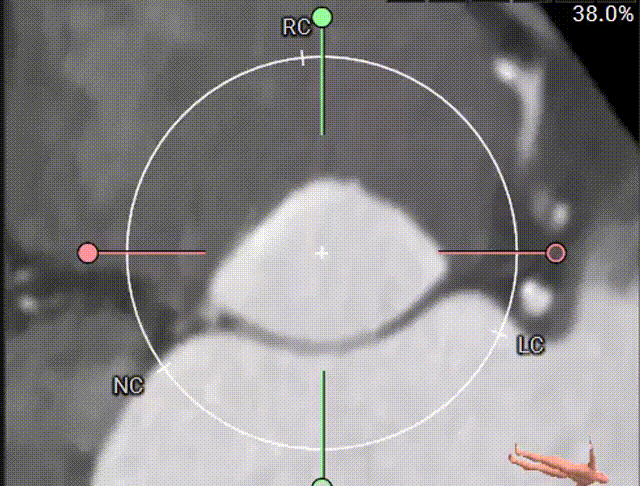

CTA肝位多平面分析

CTA锚定封堵开口平面分析

CTA模拟TEE观察左心耳

由于患者高龄,术前未行TEE检查,CTA检查后,提示患者左心耳内无血栓。多平面肝位重建分析患者左心耳开口24.6mm,模拟TEE检查左心耳开口21.5mm-24.7mm,左心耳口部封堵面分析平均开口直径24mm,肺静脉脊较长,左心耳深度较浅,拟选用WATCHMAN FLX™ 31mm封堵器封堵。